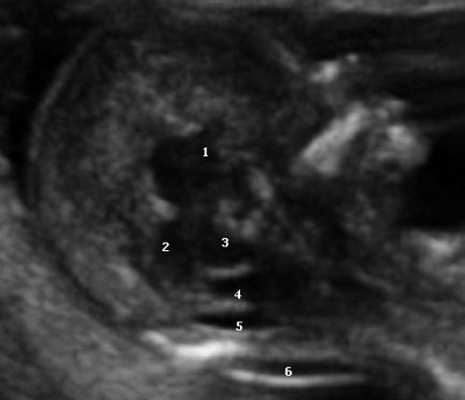

Ультразвуковая анатомия среднесагиттального скана головного мозга плода

Одним из критериев среднесагиттального корректного скана головного мозга плода в срок 11-14 недель беременности является отсутствие визуализации сосудистого сплетения и скуловой кости верхней челюсти, наличие визуализации кости носа и небного отростка верхней челюсти (рис. 1). Обязательным является наличие на скане диэнцефалона-таламуса (Thalamus), который продолжается в ствол мозга (brain stem), а также чуть ниже в средний мозг (midbrain), с продолжением в интракраниальное пространство, представляющее собой IV желудочек мозга, в котором можно визуализировать гиперэхогенное сосудистое сплетение. Между стенкой IV желудочка и затылочной костью видна анэхогенная большая цистерна головного мозга (cisterna magna). Между затылочной костью и кожей визуализируется воротниковое пространство. Для полноценной оценки структур среднего и заднего мозга необходимо оценить их наличие, размер, взаимоотношение, так как при патологии головного мозга и позвоночника эти критерии меняются.

Рис. 1. Ультразвуковая соноэмбриология структур головного мозга в среднесагиттальном скане в 13 недель беременности.

1 - диэнцефалон;

2 - средний мозг;

3 - ствол мозга;

4 - интракраниальное пространство, или IV желудочек;

5 - большая цистерна;

6 - воротниковое пространство.

Особенностями визуализации этих структур является их гипо/анэхогенность. Так, при сроках 11-14 недель беременности таламус, ствол мозга, средний мозг выглядят практически анэхогенными. Итак, нормальная ультразвуковая анатомия этих структур головного мозга плода имеет следующие особенности: ствол и IV желудочек выглядят как анэхогенные продолговатые структуры, имеющие непосредственную близость (как бы выходящие) из диэнцефалона и среднего мозга. Все выше перечисленные анатомические структуры могут быть измерены и должно быть оценено их взаиморасположение (рис. 2, а).

а) На эхограмме:

1 - ствол мозга;

2 - интракраниальное пространство, или IV желудочек;

3 - большая цистерна головного мозга;

4 - воротниковое пространство.